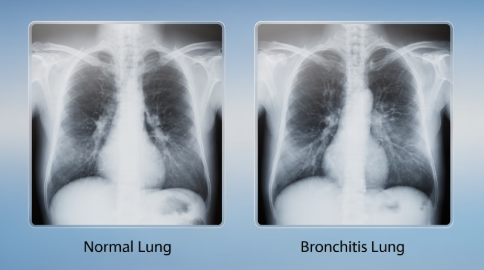

일반적으로 감기나 기관지염에서는 가래가 함께 나오는 경우가 많지만, 마른기침은 기관지 점막이 자극되거나 염증이 있을 때 나타날 수 있습니다.